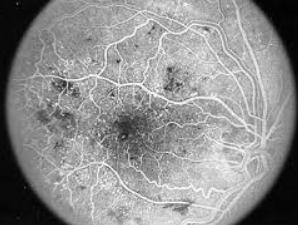

Tests that may be used include: visual fields; visual acuity; ophthalmoscopy; slit lamp examination; fluorescein angiography; and fundus photography.